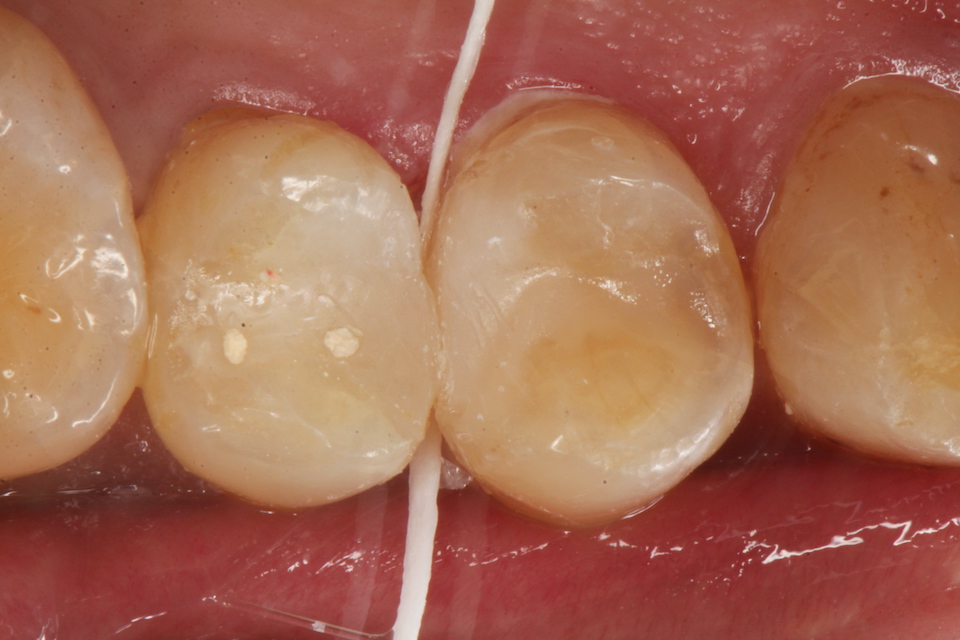

50代男性、右上45、インレー破折後の2次カリエス、咬合性外傷

露髄ギリギリなのだが、自覚症状はない。虫歯がある程度進むと染みたり痛みを感じにくくなる。それは虫歯は水素イオンの電導性がないからだ。水素イオンが歯髄の神経に到達すると痛みを感じるのだが、水素イオンの伝導は歯の主成分のハイドロキシアパタイトだけにしか起こらず、ハイドロキシアパタイトが壊れてしまった虫歯には水素イオンが伝導しない。

と言うことで、今回は​ 前回 ​のつづき右上4のCR再建過程だ。

いつものようにストリップスは使っていない。

では時系列でどうぞ